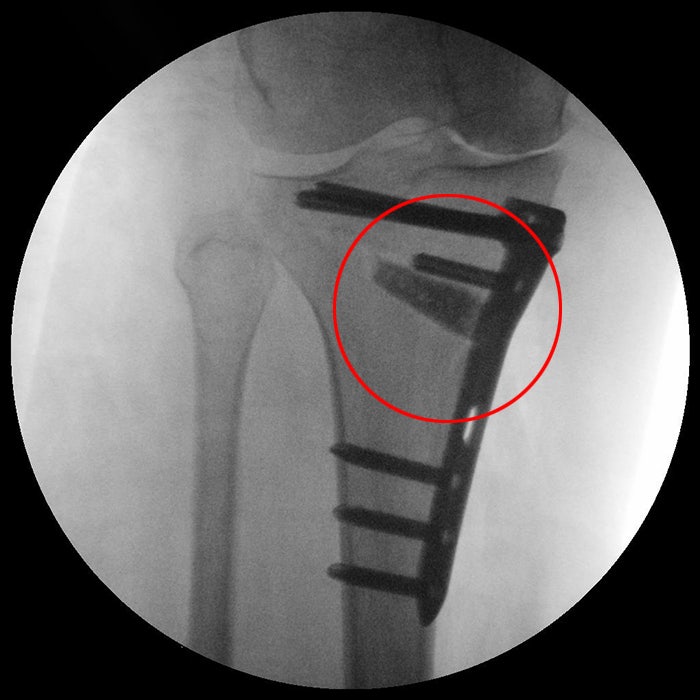

미사툰병원 / 근위경골 절골술

후만증과 다리 휘어진 다리를 교정하는 대표적인 방법은 근위 경골 절골술로, 무릎 아래 부분을 절개하여 뼈의 위치를 조정한 후 금속판과 나사로 고정하는 방법입니다. 무릎 관절이 구부러지는 방향의 아래쪽 뼈를 잘라내고 틈을 기구로 열어줍니다. 보강한 다음 자신의 뼈 또는 기타 충전재로 채웁니다. 무릎을 곧게 펴고 무릎 통증을 완화하면서 관절 각도를 정상 범위로 복원합니다. 잘못된 비틀기 자세로 인해 다리가 휘는 경우가 많은데 증상이 심한 경우에는 정확한 검진을 받아 전문의를 통한 치료계획을 세워 질병으로 이어지지 않도록 하는 것이 좋습니다.